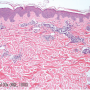

![]()

The diagnosis of shiitake dermatitis is supported primarily by its self-limited presentation, which involves the classic linear pattern of papulovesicles that appear 1-2 days after the consumption of raw or half-cooked shiitake. Histological examination illustrates a nonspecific capillary vasodilation leading to dermal edema with lymphocytic and eosinophilic infiltration and variable spongiosis.3,6 Prick-to-prick skin testing yields acceptable results in contact sensitivity cases, although studies by Nakamura et al did not support prick-to-prick testing in cases involving ingestion of shiitake.2